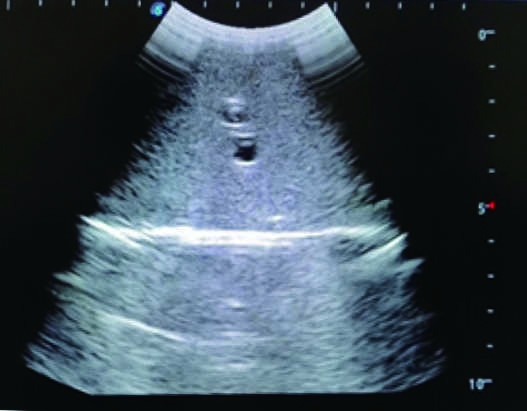

This model is an ideal choice for ultrasound-guided femoral arteriovenous puncture & abdominocentesis training with true-to-life skin feel and touch, accurate anatomical structures and real clinical ultrasound images. Realistic resistance to needle tips and correct landmarks provide excellent hands-on experience.

2)  Real clinical ultrasound images with clear anatomical structures like intestines, part of the liver, arteries and veins, etc.